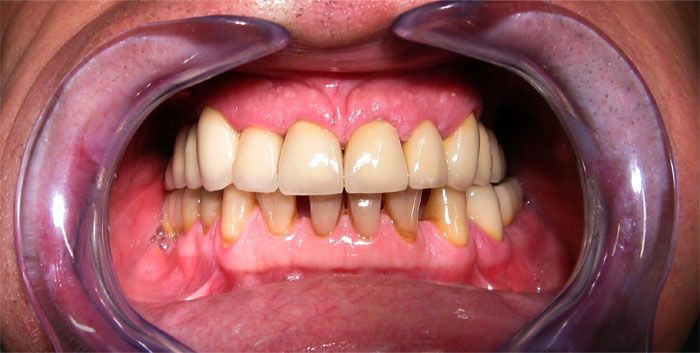

CAS N°3 Bridges complet sur 6 implants dentaires DIO mâchoire supérieure. Présence de fausse gencive sur le bridge pour compenser le déficit osseux et positionner la dentition correctement. 2 couronnes sur implants DIO mâchoire inférieure.